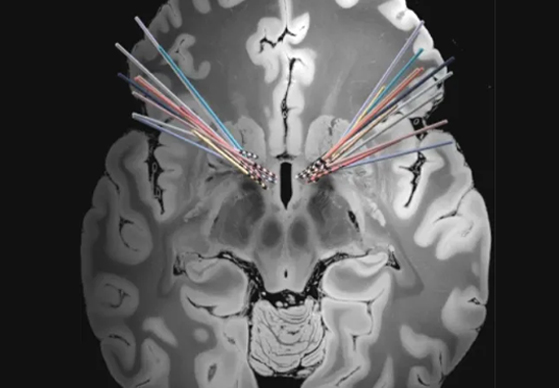

上海市精神卫生中心植入式神经刺激系统用于治疗难治性强迫症的疗效及影响因素研究项目第二例受试者开机成功!

上海市精神卫生中心植入式神经刺激系统用于治疗难治性强迫症的疗效及影响因素研究项目首例受试者开机成功!